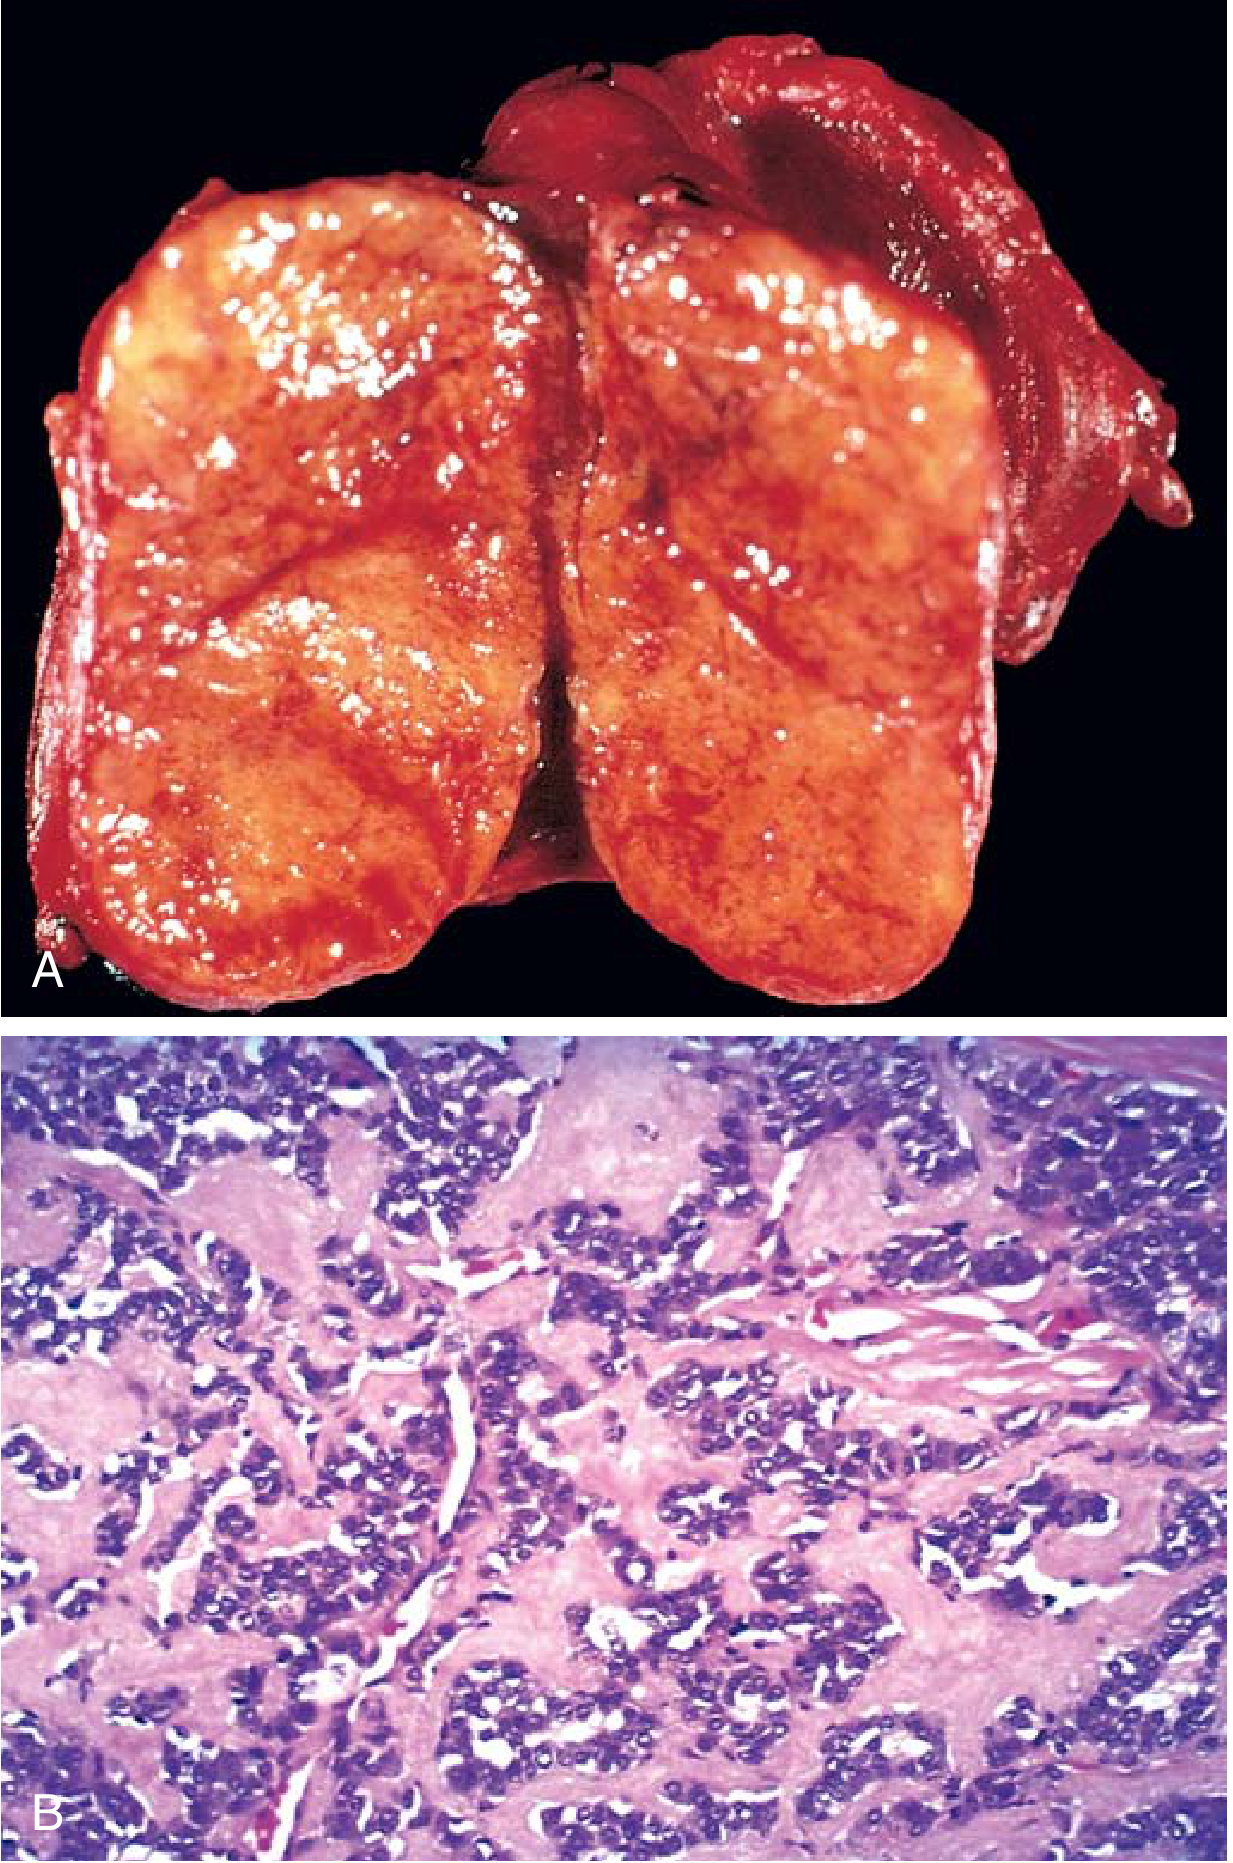

medullary carcinoma thyroid histology amyloid

│ FNA Cytology │ ← spindle/polygonal cells,

│ + IHC (calcitonin) │ amyloid